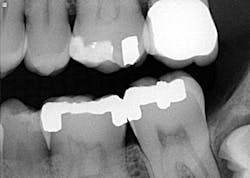

A healthy, 38-year-old male presented to the office for a comprehensive exam. His blood pressure was within normal limits, and no medications were being taken. Bitewing radiographs were taken, and it was noted that there was a cystlike lesion on what appeared to be a mesial impaction of no. 17. A panoramic radiograph indeed revealed a large, radiolucent/cystlike lesion surrounding a mesial/inferior-positioned no. 17. The widest point of the cyst measured approximately 3 cm. The patient reported knowing about the lesion but was not inclined to have it removed because it was not bothering him. The area was not tender to palpation; tooth no. 18 had normal pocketing and tested normal to cold, percussion, and bite.